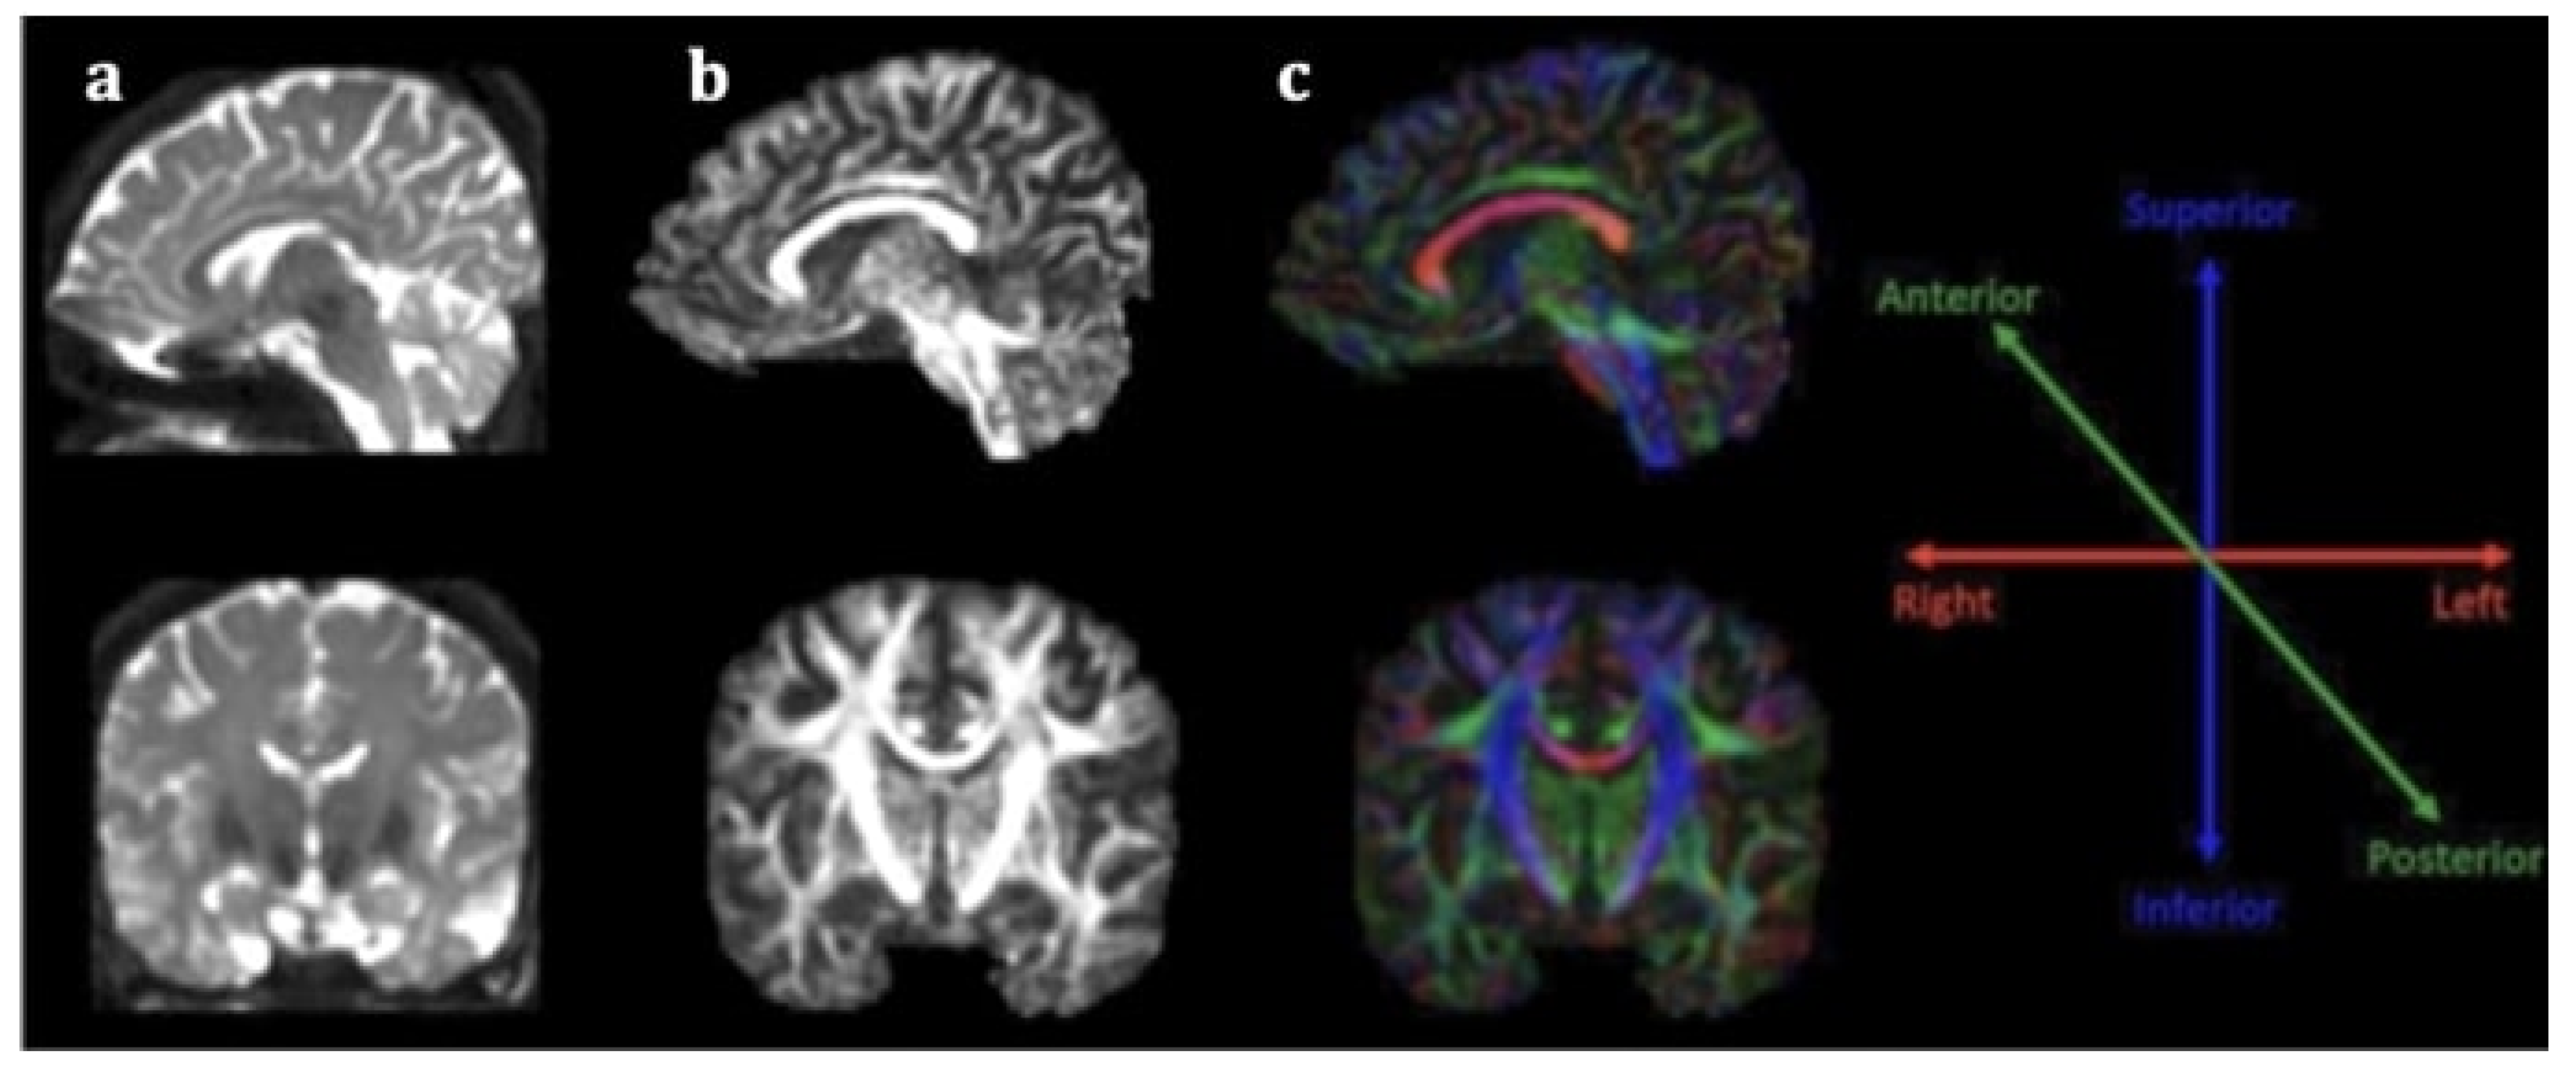

Stroke diagnosis has been facilitated by the incorporation of advanced neuroimaging modalities in clinical practice, especially diffusion weighted imaging (DWI), a technique based on the motion of water molecules. Nevertheless, conventional magnetic resonance imaging (MRI) is incapable of accurately illustrating microstructural impairment on white matter (WM) tracts, rendering its role in predicting stroke outcome limited. Conversely, diffusion tensor imaging (DTI) is an extension of this modality for in vivo mapping of white matter (WM) directionality and organization, allowing the qualitative and quantitative evaluation of major WM tracts and their microstructural integrity [6]. DTI is based on the random diffusion of water molecules [7]. In WM, water diffusion is slower perpendicular to the fibers, but it occurs faster along their longitudinal axis, producing anisotropic diffusion. The extent of anisotropy is influenced by integrity and organization of the WM tract and water diffusion mobility generated by axonal membranes and their myelin sheaths. Different computational algorithms are used to track different WM bundles and study WM organization in healthy participants and different disease samples [8]. The most widely employed DTI parameters are fractional anisotropy (FA), mean diffusivity (MD), axial diffusivity (AD), and radial diffusivity (RD). FA measures the preferential directionality of diffusion and is quantitatively expressed in numerical values between 0 and 1. High FA values indicate a greater degree of preferential directionality (anisotropic diffusion). Such a high degree of preferential directionality is commonly observed in highly organized WM tracts. On the other hand, low FA values indicate less preferential directionality of water molecules (isotropic diffusion). Low FA values close to 0 are observed in gray matter and cerebrospinal fluid. MD indicates the diffusion magnitude, AD describes the diffusivity along the dominant diffusion direction, and RD portrays the average diffusivity of two shorter eigenvectors [7]. It has been suggested that AD is mostly related to axonal degeneration whereas RD is mostly linked to demyelinating processes [9]. DTI offers directional information on water molecule diffusion and provides additional maps, including the fractional anisotropy (FA) map and the color-coded directional map (Figure 1). The color-coded directional maps are based on the convention that the blue color represents the water molecules that diffuse in an inferior–superior direction, the green color represents that water molecules that diffuse in an anteroposterior direction, and the red color represents the water molecules that diffuse in a left–right direction. Although DTI has not yet been incorporated in routine clinical care in stroke, a growing body of research suggests that it is a promising imaging biomarker for stroke recovery, owing to its ability to imprint white matter tract integrity in detail [9].

Figure 1.

Sagittal (first line) and coronal (second line) section of DTI data (a), fractional anisotropy map (b) and color fractional anisotropy map (c). The color-coding of the white matter tracts in the color fractional anisotropy map follows the assumption: red for left–right-oriented fibers, blue for superior–inferior-oriented fibers and green for anteroposterior-oriented fibers.